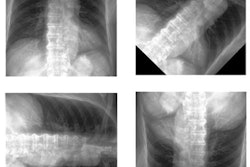

The researchers applied simple transformations to each test image to simulate the following real-world variations:

- Rotations

- Flips

- Brightness adjustments

- Contrast adjustments

- Inverted pixels

- Addition of a standard radiological laterality marker

- Resolution changes from a baseline of 1024x1024

For example, for 180° rotations, predicted bone age was significantly lower (97.8 months vs. 135.2 months, p < 0.0001) and MAD was significantly higher (45.2 months vs. 6.9 months, p < 0.0001) with 30% more clinically significant errors (p<0.0001) compared with baseline images.